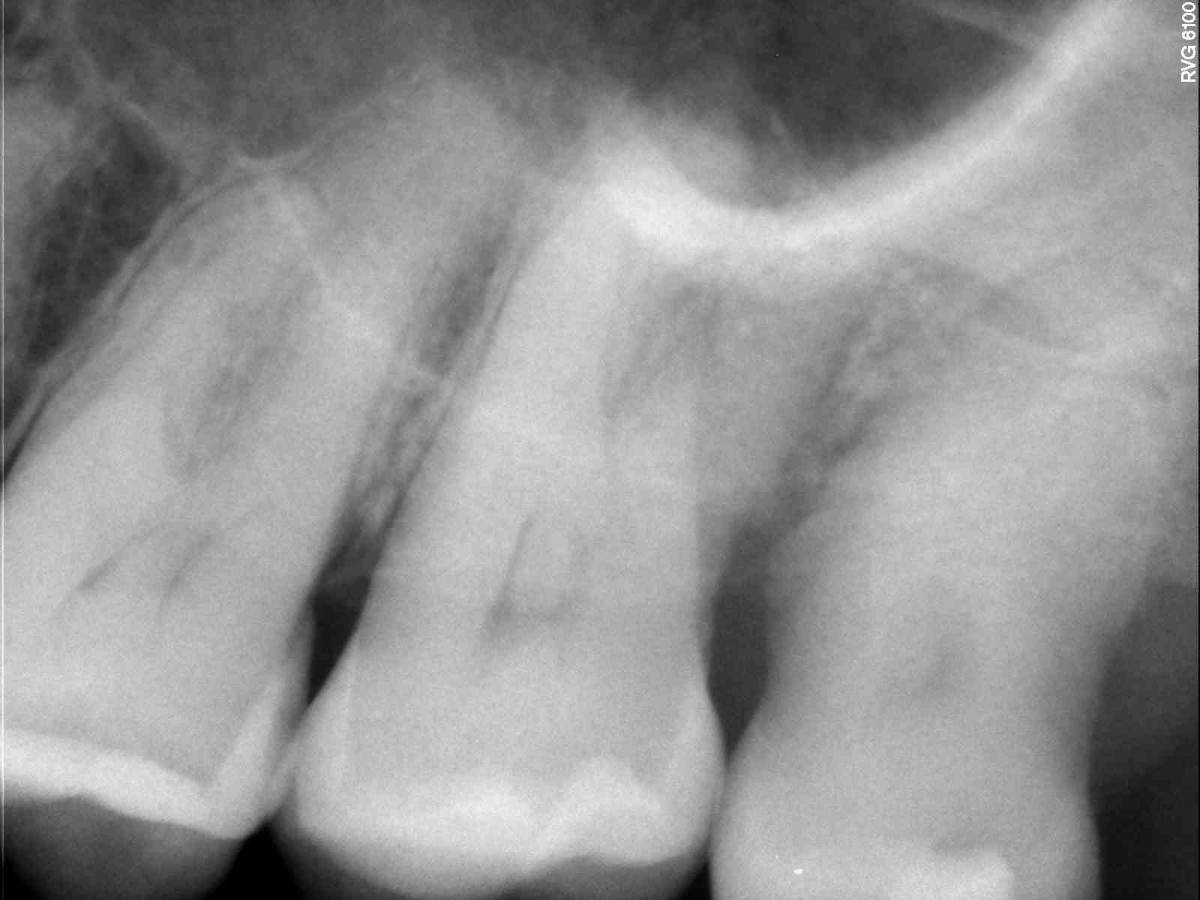

Игель Опубликовано 27 апреля Поделиться Опубликовано 27 апреля Добрый день. Верхние 6-7-8 слева. Больно жевать, ночью была пульсирующая боль. Десна воспалена. Сходила к врачу. Рентген прикладываю. Врач сказала нет пульпита. Идти к Лору на предмет гайморита или все же дело в зубах? Отчего может так болеть? Раньше никогда не было пульпита. 53 года, регулярно посещаю стоматолога Ссылка на комментарий

red_butler Опубликовано 1 мая Поделиться Опубликовано 1 мая Здравствуйте, нужен очный осмотр, мне не нравиться Ваш зуб мудрости, скорее всего причина в нём Ссылка на комментарий